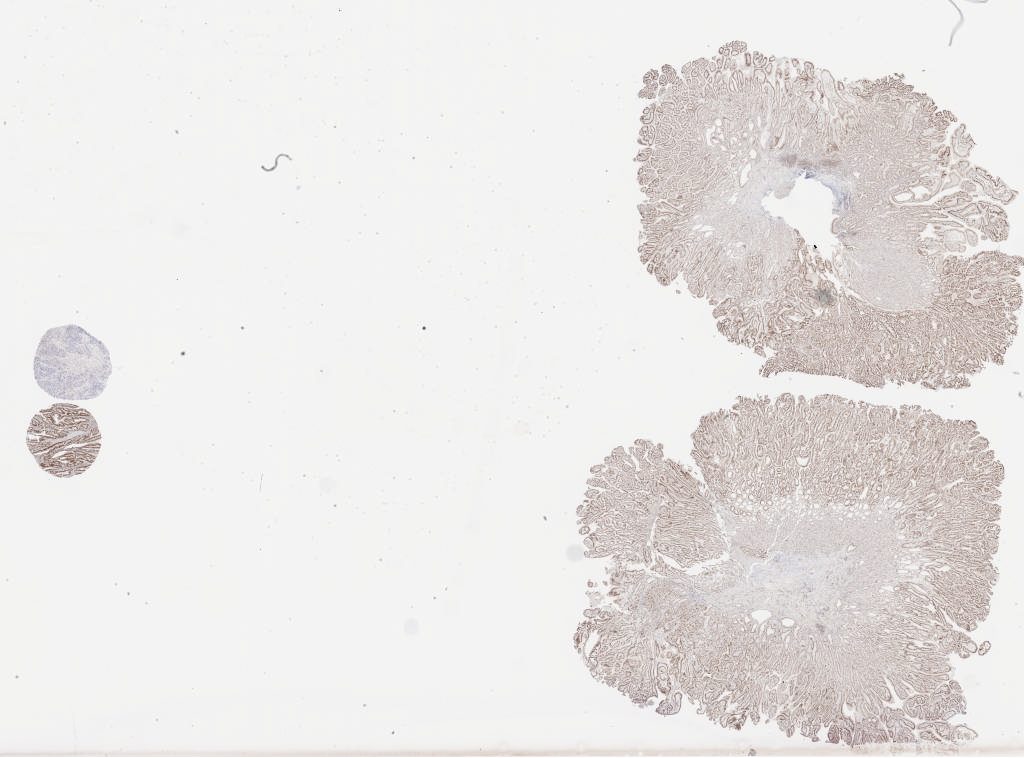

pms 1a.svs

91632

x

67744

@

40X